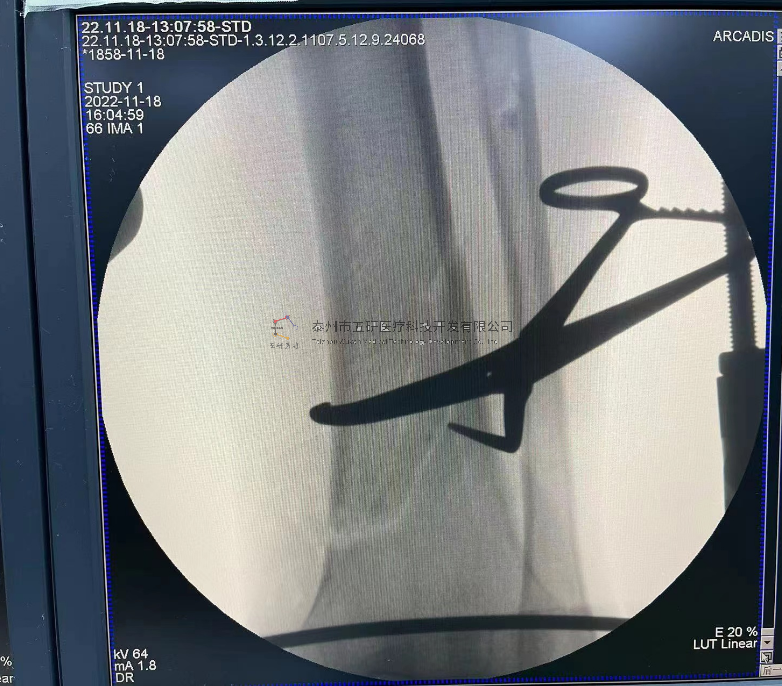

// 下肢骨折

【所屬科室】中國(guó)中醫(yī)科學(xué)院望京醫(yī)院創(chuàng)一科

【基本資料】患者,男,65歲

【患者情況】脛骨遠(yuǎn)端骨折伴腓骨骨折

【影像圖片—術(shù)后】

10.png

11.png

12.png